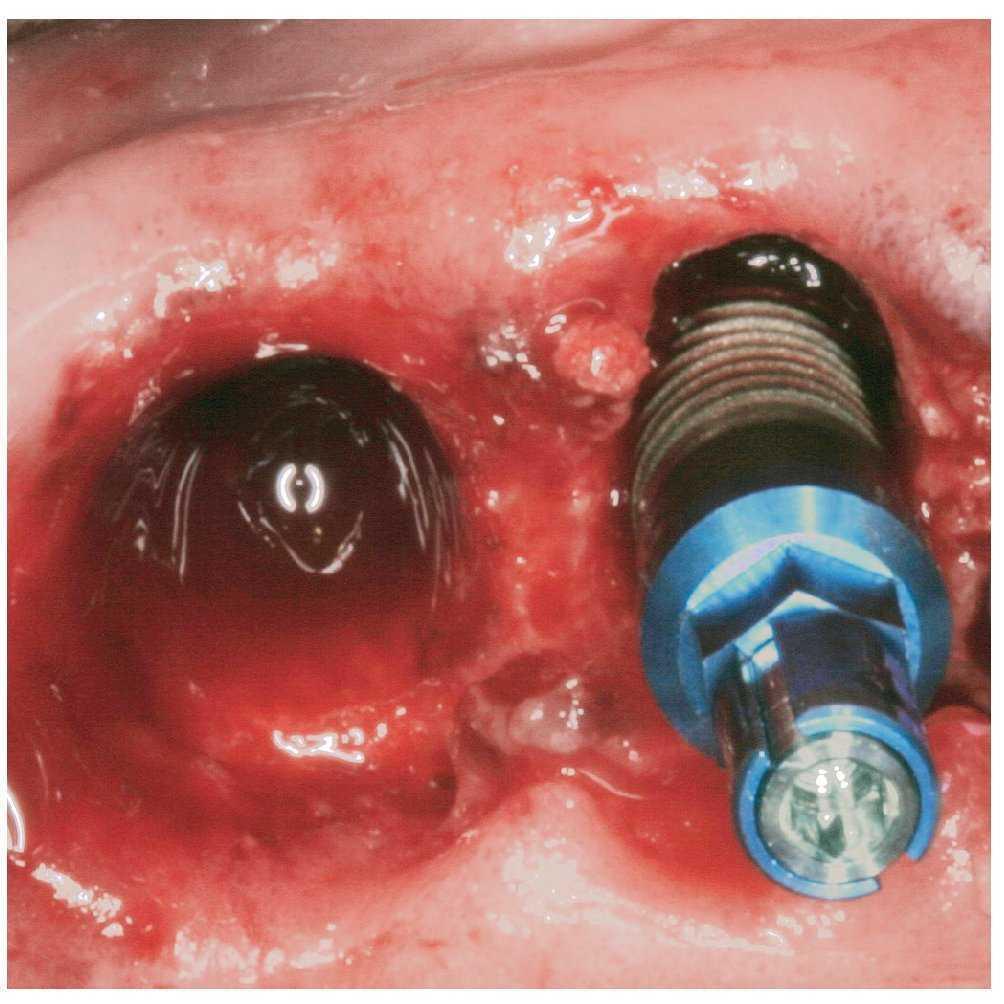

La posibilidad de colocar implantes endoóseos en la consulta dental general dependerá de forma decisiva de la situación del lecho óseo y de los tejidos blandos. Una vez emitido el diagnóstico, siempre que el esfuerzo quirúrgico de compensación sea elevado y rebase los límites de la experiencia personal y de las posibilidades de la consulta, será necesario contar con la colaboración de un odontólogo experto en cirugía implantológica o de un cirujano maxilofacial. Para la colocación de implantes en lechos con suficiente volumen óseo el odontólogo dispone de modernos sistemas de implante de reconocidos fabricantes que ofrecen un elevado grado de seguridad si se respeta el protocolo quirúrgico correspondiente. Las marcas realizadas con láser y los topes de profundidad, por ejemplo, permiten evitar una sobreinstrumentación y previenen lesiones de estructuras anatómicas adyacentes a la cresta alveolar (fig. 1).

Figura 1. Las marcas realizadas con láser y el uso de topes de profundidad evitan la sobreinstrumentación.